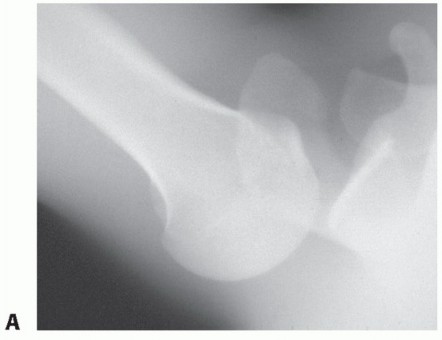

Radiographic evaluation includes a three-view trauma series of the shoulder, including a true anteroposterior (AP) view of the shoulder, a scapular lateral, and, more importantly, an axillary view.

A Velpeau axillary view can be substituted if the attempted axillary view is impossible because of painful abduction of the shoulder.

Axillary radiographs of patients with a voluntary component to their instability can be taken while the patient reproduces and maintains the subluxation episode to document the direction (FIG 2A).

FIG 2 • A. Axillary radiograph of patient with voluntary posterior instability, reproducing the instability while taking the radiograph. B. CT scan demonstrating significant posterior glenoid retroversion in a patient with posterior instability.

A computed tomography (CT) scan can be helpful to evaluate humeral head defects and associated fractures of the tuberosities, humeral shaft, and posterior glenoid rim. Significant posterior glenoid

retroversion can also be demonstrated on CT scanning (FIG 2B*).